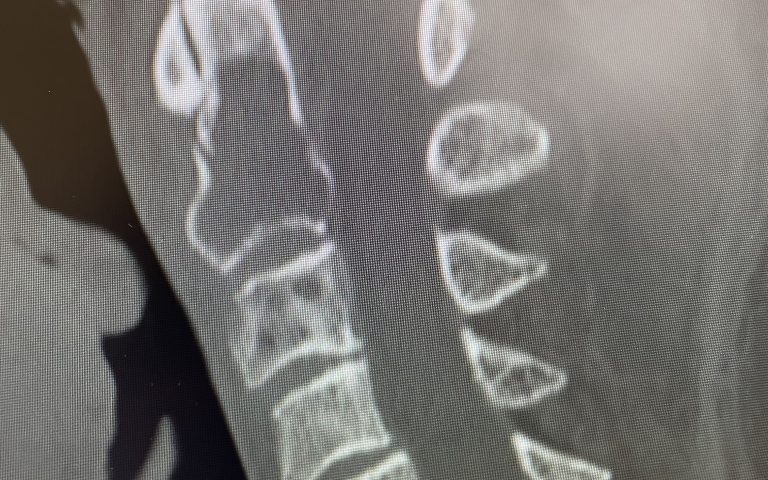

Fig 1: Sagittal and axial CT scan showing a lyric C2 lesion with extension into the posterior elements on the right side

Here is a tough case: This is a 72 year-old male who presented with several months of progressive neck pain without symptoms of the arms or legs. He had a history of prostate cancer for which he was treated. He had a biopsy of a hip lesion which was consistent with Paget’s disease, a benign but aggressive disease of the bone. He had imaging studies that were consistent with a destructive lytic C2 bony vertebral body lesion with extension into the posterior bony ring and possibly affecting C3 vertebral body (Fig 1). The patient’s urologist didn’t believe the patient had metastatic prostate cancer since his PSA was not elevated. The lesion itself was also not consistent with metastatic prostate cancer as they are usually blastic or bone forming lesions not bone destroying. His oncologist had initially sent us the patient with the thought that this was Pagets’s disease. Paget’s disease rarely affects the cervical spine and the bony appearance is more heterogeneous with a “picture-frame” appearance and hyperdense and not lytic. The patient underwent a PET scan which was “hot” consistent with malignant tumor. The patient underwent a bone marrow biopsy and had blood work consistent with a multiple myeloma diagnosis. The patient underwent radiation treatment with 25 fractionated cycles. The patient was given one percocet to control his pain by his oncologist.